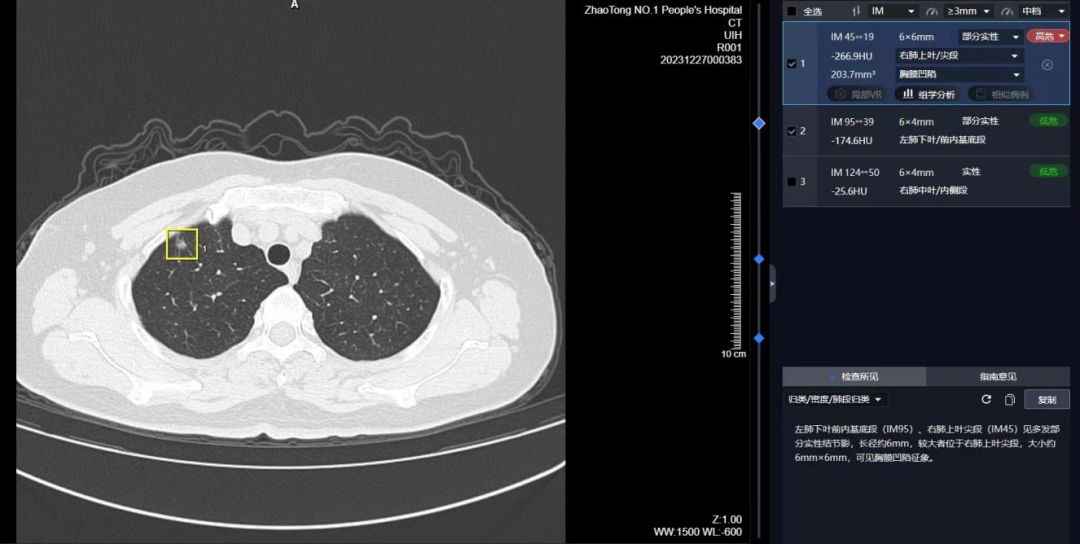

1 、病灶直径小于0.5cm,定义为微小结节,恶性肿瘤可能性小于1%。

2、病灶直径在0.5-1cm,定义为小结节,恶性肿瘤可能性25-30%。3、大于3cm的称为肿块。直径大于2cm的肿块,恶变率在64-82%。

实性结节:

磨玻璃结节:

部分实性结节:

肺癌高危结节